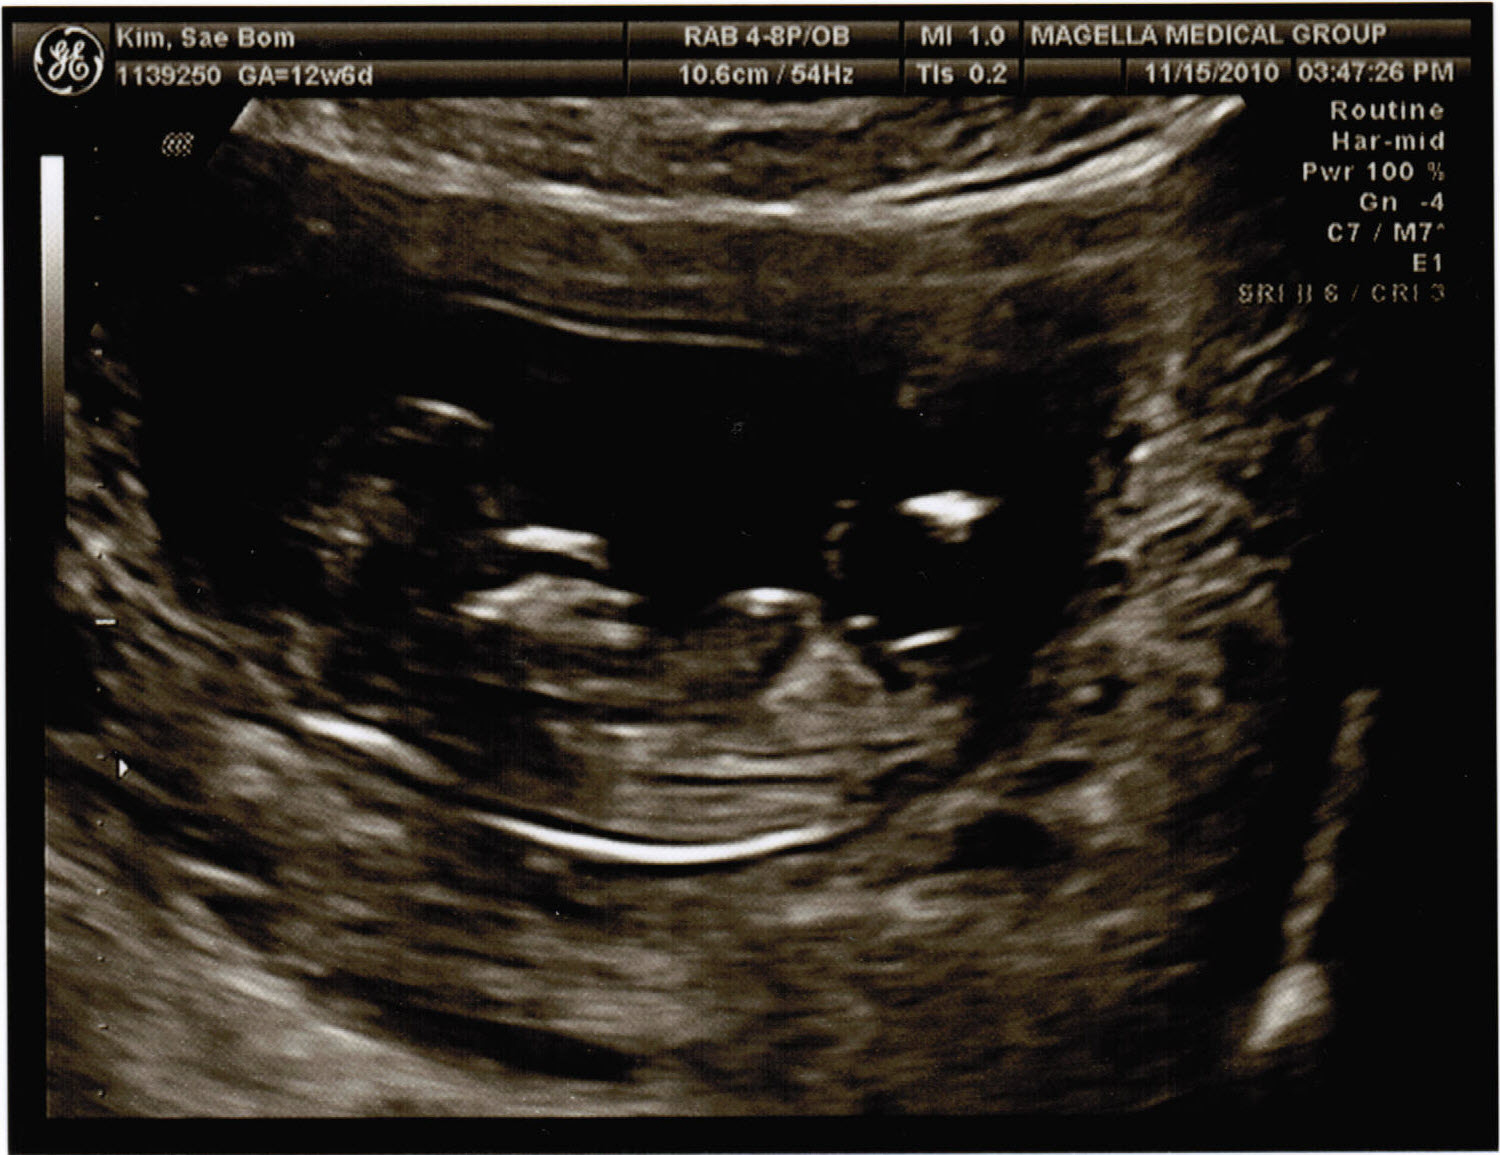

Okay so this is this second time we went to get the sonogram and have a clear shot of how it’s growing and if everything looks pretty normal. But i doubt they could really tell if anything was wrong at this point. Could they? I don’t know but once again i’m in awe just by hearing the heart beat alone. And to now see the full body inside Lisa just adds to the whole experience. I can’t wait!